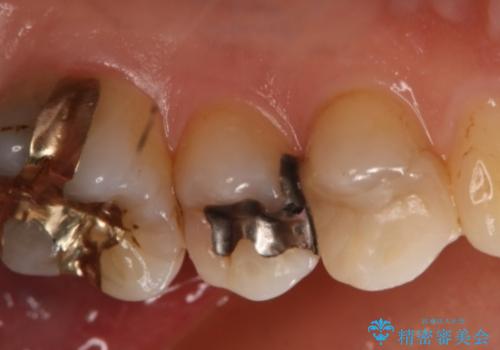

- 左上奥歯の銀歯のやり変えを希望された患者様です。

白くしたいとの事だったので形態・切削量を考慮し、セラミックインレーでの治療を計画しました。